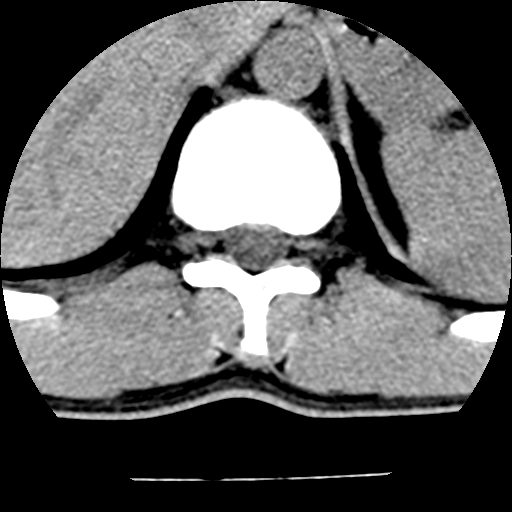

男,31岁,从6米高处坠落伤两天,腰背部疼痛,临床要求ct扫描胸10-腰1。请大家帮忙看看骨质有问题吗?

t12、l1锥体前缘轻度楔形变,平扫示椎体前缘骨小梁欠规整,第9幅图示椎体前缘骨质不连续,结合外伤史考虑椎体轻度压缩骨折。

楼主扫描层厚可能较大,每个椎体只有三个层面.

从所示层面分析,无明确骨折征象,象类似病人我个人会建议mri除外骨挫伤.

从上查骨窗第九片椎体前缘皮质显示断裂.压缩骨折?